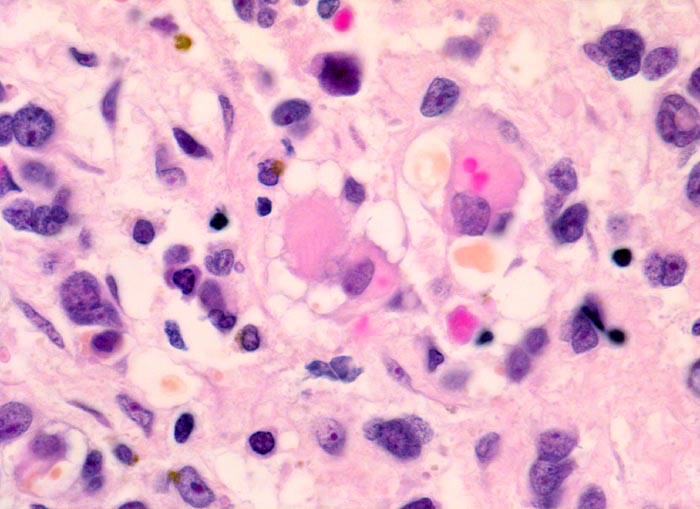

• Dominierend sind in diesem Tumor teils mehrkernige Rhabdomyoblasten mit reichlich eosinophilem Zytoplasma und exzentrischem Zellkern. Die Querstreifung des Zytoplasmas ist in der HE Färbung nur andeutungsweise erkennbar.

• "Spinnwebenzellen" mit peripheren Zytoplasmavakuolen.

Das makroskopische Bild ist uncharakteristisch und variiert in Abhängigkeit von der Lokalisation. Fokale Nekrosen und zystische Degeneration sind häufig. Es werden verschiedene histologische Subtypen unterschieden, welche charakteristische molekulargenetische Aberrationen aufweisen und mit unterschiedlichen Prognosen assoziiert sind. Die beste Prognose haben botryoide und spindelzellige Rhabdomyosarkome gefolgt von embryonalen Rhabdomyosarkomen (intermediäre Prognose) und alveolären bzw. pleomorphen Rhabdomyosarkomen (schlechteste Prognose). Therapieantwort und Prognose hängen neben der Histologie auch von der Lokalisation ab. Embryonale Rhabdomyosarkome zeigen ein breites morphologisches Spektrum. Dieses reicht von wenig differenzierten Tumoren, die nur mittels Immunhistochemie und Elektronenmikroskopie diagnostizierbar sind zu gut differenzierten Tumoren, die fetaler Muskulatur ähneln. Oft findet sich eine Mischung von wenig differenzierten kleinen, runden und/oder spindeligen Zellen und eine variable Anzahl differenzierter Rhabdomyoblasten mit reichlich eosinophilem Zytoplasma. Die Rhabdomyoblasten können rund, spindelig, kaulquappenförmig oder spinnwebenförmig sein. Besser differenzierte Zellen enthalten reichlich Zytoplasma mit Querstreifung, welche allerdings teilweise nur elektronenmikroskopisch nachweisbar ist.